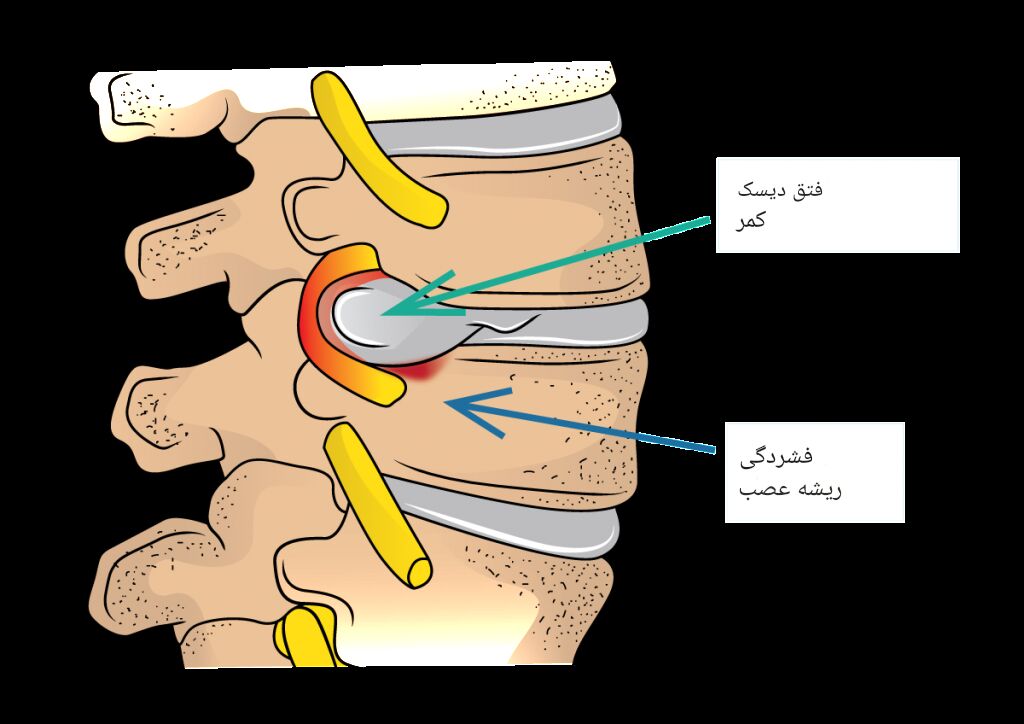

3. فشار بر عصب زانو یا پا

گاهی درد ناشی از فشار عصبی باعث واکنش دفاعی بدن میشود. در این شرایط زانو برای کاهش درد بهطور ناگهانی خم میشود و فرد احساس خالی شدن زانو را تجربه میکند.

| فشار عصبی | ایجاد درد و خم شدن غیرارادی |